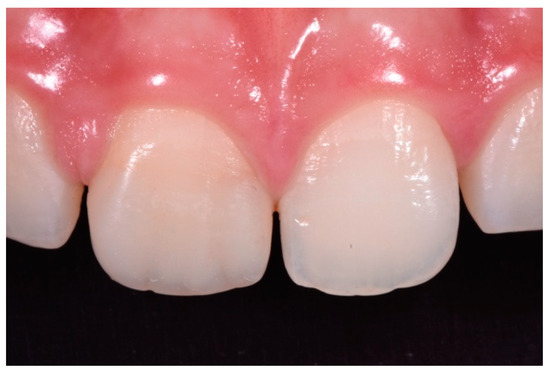

Figure 15.

Three months post-operative. Reprinted from Restauri diretti nei settori anteriori, G. Paolone, S. Scolavino, © 2021, with permission from Quintessence Publishing Italy.

Finishing and polishing procedures were performed with a diamond bur (WL 268 014 Horico, Berlin, Germany), silicone points (Identoflex, Kerr, Bioggio, Switzerland) brushes (Jiffy Goat Air Brushes, Ultradent Products, South Jordan, UT, USA), and diamond pastes (Diamond Polish Mint, Ultradent Products, South Jordan, UT, USA) (Figure 13 and Figure 14). Satisfactory clinical and radiographic outcome was considered satisfactory at 3-months, 1-year, and 5-years post-operative (Figure 15, Figure 16, Figure 17, Figure 18 and Figure 19).